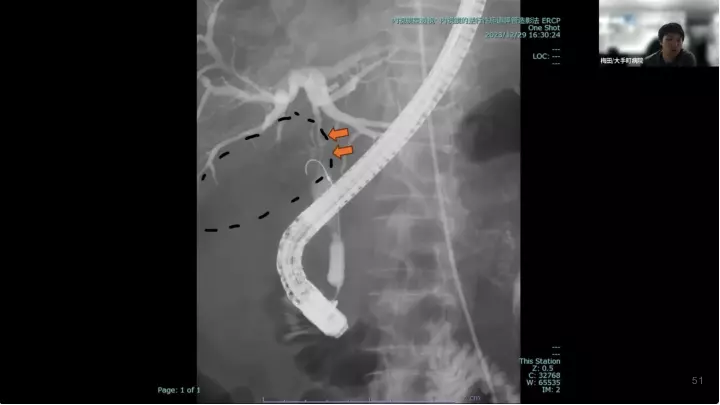

外科医目線の~急性胆嚢炎~治療編